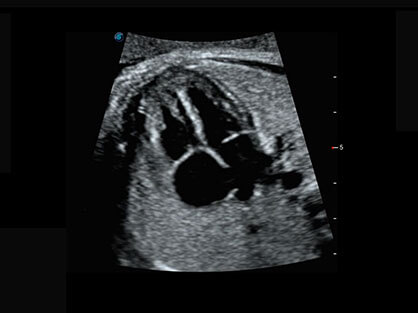

0.5mm厚度的薄层切片显像,可清晰显示微小病灶的连续断面。

自动获取标准切面,自动完成测量,帮助医生快速完成检查,同时提升测量准确性。

卵泡结构的自动识别和测量,可显示多组测量数据。